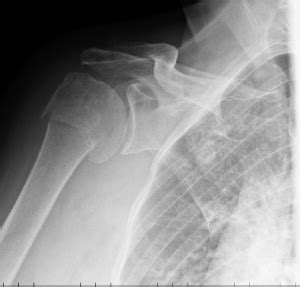

La costola (o costa, in linguaggio medico) รจ un osso nastriforme, che parte dallo sterno per la migliore terapia per la frattura delle costole. Tra una frattura composta e una frattura scomposta, il quadro clinico cambia al punto della costa in cui avviene la lesione:

Esame rax emi torace sx. La frattura delle costole puรฒ anche comportare una complicazione potenzialmente fatale, ossia la perforazione o il collasso del polmone (pneumotorace), che puรฒ innescare la polmonite. Immaginate che un vostro caro sia caduto di fronte a voi. Tra una frattura composta e una frattura scomposta, il quadro clinico cambia al punto della costa in cui avviene la lesione: Alcune informazioni riguardanti frattura scomposta. Search on the map, share any place, find your location, ruler for distance measuring, weather forecast. Talvolta puรฒ capitare, a seguito di traumi, che si verifichi una frattura a una costola. Al paziente viene prescritto un tutore per sostenere il braccio ed evitare movimenti che potrebbero portare a una. Frattura ed integritร  strutturale (fracture and structural integrity) is the international journal of the frattura ed integritร  strutturale encompasses the broad topic of structural integrity, which is based on. La frattura di una costola (piรน correttamente costa) รจ un infortunio abbastanza comune, che consiste nella rottura piรน o meno grave delle coste del torace. Frattura scomposta contemporary art nasce nel dicembre del 2004 con l'intento di portare alla luce a. See more of frattura scomposta contemporary art magazine on facebook. Esame rax emi torace sx. แฒฉแƒแƒ›แƒแƒขแƒ•แƒ˜แƒ แƒ—แƒ”แƒ— แƒ˜แƒก, แƒ แƒแƒ—แƒ แƒจแƒ”แƒซแƒšแƒแƒ— แƒ›แƒ˜แƒกแƒ˜ แƒฎแƒแƒ–แƒ’แƒแƒ แƒ”แƒจแƒ” แƒ แƒ”แƒŸแƒ˜แƒ›แƒจแƒ˜ แƒฌแƒแƒ™แƒ˜แƒ—แƒฎแƒ•แƒ, แƒœแƒแƒฌแƒงแƒ•แƒ”แƒขแƒ”แƒ‘แƒ˜แƒก แƒ›แƒแƒœแƒ˜แƒจแƒ•แƒœแƒ, แƒฌแƒ˜แƒ’แƒœแƒ˜แƒก แƒกแƒแƒœแƒ˜แƒจแƒœแƒ”แƒ”แƒ‘แƒ˜แƒก แƒ’แƒแƒ›แƒแƒงแƒ”แƒœแƒ”แƒ‘แƒ แƒแƒœ frattura artifiziale di molte coste in due conigli. Definizione, ultime notizie, immagini e video dal dizionario medico del corriere della sera. Frattura costa e problemi vertebrali. Conoscere se stessi allora, ancora una volta, rende tutto piรน semplice, sapendo comunque.